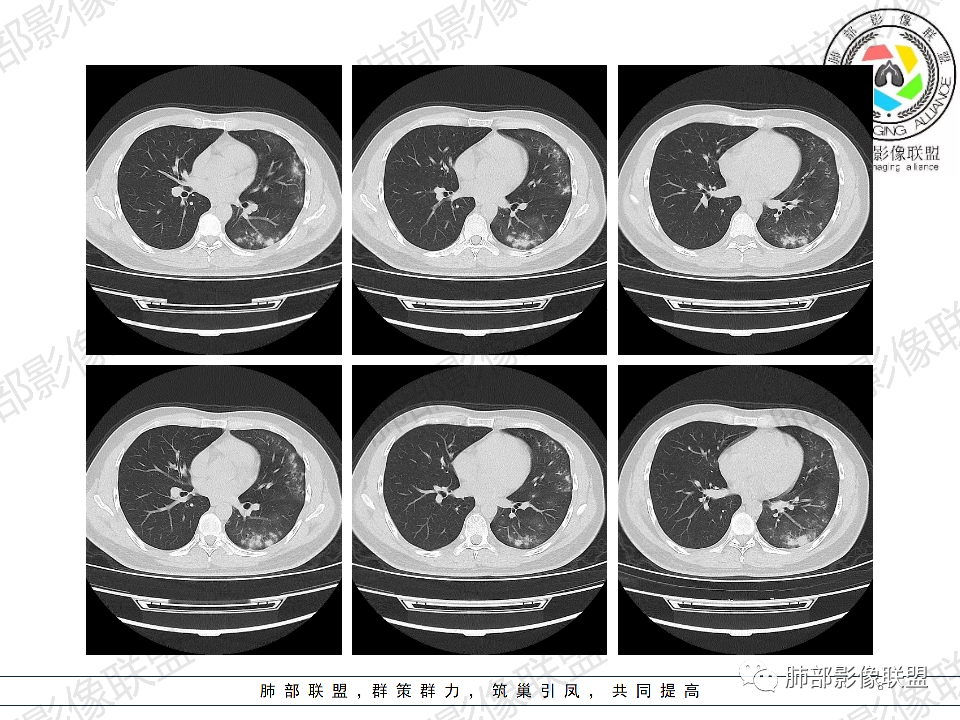

年轻男性,有HIV病史,免疫力缺陷病史,CD4明显减低,左肺胸膜下多发大小不等结节影,部分侧向融合,平行于胸膜,周围伴有模糊的GGO,部分结节与血管相连,血管束增粗,考虑隐球菌,建议查隐球菌荚膜实验,脑脊液隐球菌荚膜,鉴别:CMV(局限性比较少见)

年轻人,男性,HIV阳性,双肺多发斑片状,结节状阴影,以胸膜下分布为主,病灶与支气管血管束垂直生长,周围可见磨玻璃影,考虑肉芽肿病变,隐球菌感染可能性大,鉴别GPA,胞子菌肺炎。

双肺胸膜下多发大小不等结节伴晕征,部分似有融合

左肺多发大小不等结节影,部分融合,胸膜下分布为主,平行于胸膜,周围伴有磨玻璃晕,考虑隐球菌,鉴别:PJP

年轻男性,HIV阳性,胸闷喘憋,双肺胸膜下多发斑片结节影,周围伴晕,部分融合,白细胞低,CD4明显减低,考虑机会性感染性病变,隐球>PCP>结核

青年男性,HIV阳性,白细胞及淋巴细胞显著降低,CRP增高,胸闷气喘一周,影像为双肺胸膜下平行于胸膜分布的多发大小不等结节伴晕,单从影像上看,隐球是要首先考虑,但是不好解释临床症状。需要鉴别:1、曲霉所致IPA,临床有粒缺基础,胸闷一周要考虑,但影像不是典型的血道或气道分布又存疑,2、马尼,CD4低,HIV基础,要考虑,但是否有旅广史?另外纵隔淋巴结无肿大,肝脾不肿大,可能稍小。3、PCP,HIV基础,CD4低,胸闷气喘要考虑,影像分布不典型。4、腺病毒或EB病毒感染,HIV基础,影像改变要考虑,但是发病无发热,存疑。5、结核,临床与影像均不典型。可能小。综上,隐球>曲霉>PCP>马尼>病毒感染。下一步,查隐球荚膜抗原,NGS找病原体。

我们科里读片的时候,也是觉得主诉特别像PCP的主诉。但是影像学表现,双肺胸膜下多发小结节,结节周围带晕,蘑菇兄弟手拉手,有的结节侧向融合整体与胸膜平行。影像符合隐球。我们科里艾滋合并隐球菌真正确诊出来的很少。所以要说总结HIV合并隐球的病例特点,我没有发言权

肺隐球菌多分布在肺野外带或胸膜下区域,下叶多见,可能余隐球菌更容易在胸膜下肺泡中定植或蔓延有关;显示腺泡结节,然后取决于宿主免疫,可以入血,然后血播

5、分布:病灶分布多位于胸膜下,可紧贴胸膜,也可与胸膜邻近,病灶长轴与胸膜平行。(划重点,分布特点非常重要)

8、晕征:病变早期可出现磨玻璃晕征,为周围炎性渗出或肺间质受累。

10、“葫芦兄弟”:邻近胸膜多发结节,形态密度类似,可簇状分布,较少多形性,没有新旧不等。